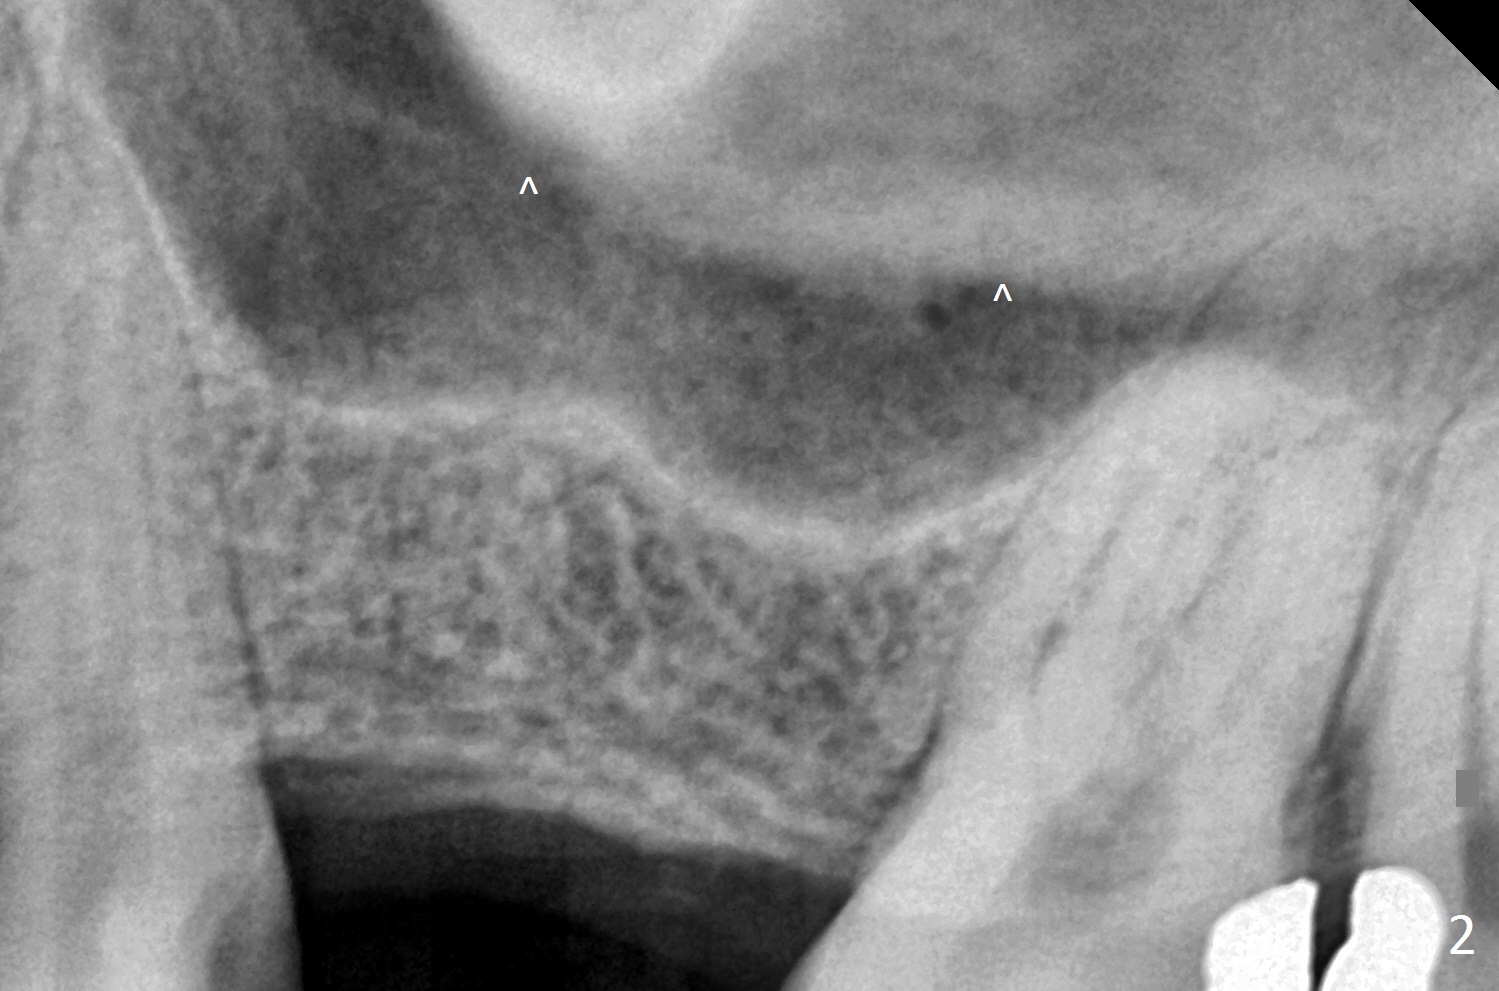

Place Implant Between Two Layers of Sinus Floor

A 47-year-old man agrees implant at #14 (Fig.1). He worries about the bone height. There appear to be 2 layers of the sinus floor (Fig.1,2 (arrowheads: upper one)). The horizontal plate of the palate is indicated by *. An IBS implant will be placed between the 2 layers of the sinus floor as shown in Fig.3. Osteotomy is initiated with Magic Split, followed by Magic Expanders (initial depth 9 mm gingival level) or Magic Lifter. Before placing the implant, insert PRF and Allograft with a condenser with a stopper.